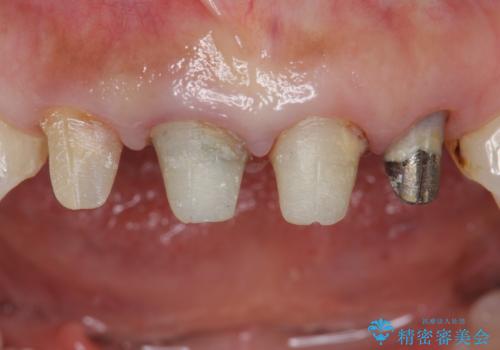

色調・適合ともに改善するために一度被せ物を外し、歯の形を整えた後に新しい被せ物を装着していきます。

歯ぐきの炎症を抑えつつ、被せ物と歯との境目がわからなくなるよう被せ物を装着しました。